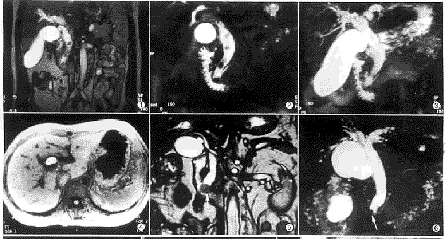

图1~3 男性,65岁。胆总管多发结石。True FISP冠状面(图1)和MRCP断面图(图2)清楚显示结石。MRCT MIP像未能显示结石 图4 男性,47岁。胆囊结石。FLASH T1WI上结石呈高信号 图5、6 男性,71岁。壶腹癌(箭头)。True FISP冠状面(图5)清楚显示胆总管扩张和软组织肿块。MRCP未能显示肿块 图7 女性,61岁。肝门胆管癌。左右肝管断端呈圆锥形 图8 女性,56岁。胰头癌。胆总管下端呈不规则鼠尾状狭窄,胆管胰管扩张 图9、10 男性,52岁。胰腺癌肝转移。FLASH T1WI动态增强门静脉期(图9)右肝转移灶清楚显示(箭头)。True FISP未能显示转移灶全貌(白箭头),胆囊区低信号影(黑箭头)为肠道气体造成的磁化率敏感伪影

2.2.1 结石的显示: 单发结石4例,多发结石26例,结石大小为0.3~2.6cm,合并胆管扩张20例。扩张的胆管形态较均匀,多呈“枯树枝”状,梗阻端形态多呈“杯口”状和“截断”状。与胆汁的信号比较,在True FISP像、MRCP断层像和MRCP MIP像中结石显示为低信号,部分结石在MRCP MIP像显示不满意(图1~3)。其中有5例(5/30,16.7%)较大的结石中心部位有高信号。在T1加权FLASH序列中20例(20/30,66.7%)为低信号,与胆汁不易分辨;5例(5/30,16.7%)为中等信号,可分辨;5例(5/30,16.7%)为高信号,与胆汁分辨清楚(图4)。结石患者中,1例合并肝脓肿,表现为T1加权呈多发低信号灶,T2加权呈不均匀高信号。1例合并急性胰腺炎,5例合并急性胆囊炎,表现为胰腺或胆囊肿大,边缘模糊,周围有水肿渗出等异常改变。

2.2.2 肿瘤的显示: MRCP断层像能部分显示肿瘤形态。True FISP像可较清楚地显示肿瘤的外形轮廓、大小及侵犯范围。而在MRCP MIP像上则难于显示(图5、6)。结合以上几种成像方法,发现30例肿瘤所致的扩张胆管形态多呈“软藤”状,其近端有以下几种形式:截断性梗阻最常见,有17例(17/30,56.7%),其断端呈“截断”状或“杯口”状(图5、6);锥形或圆锥形狭窄梗阻6例(6/30,20.0%)(图7);不规则状狭窄4例(4/30,13.3%);鼠尾状狭窄梗阻3例(3/30,10.0%)(图8)。True FISP像可显示2例门脉受侵、1例十二指肠受侵征象。其他序列显示不满意。1例肝内转移灶True FISP序列显示不满意,而T1加权图像等显示良好(图9、10)。